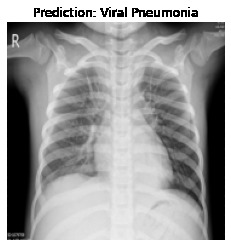

Currently, there is an urgent need for efficient tools to assess the diagnosis of COVID-19 patients. In this project, we propose a constructive solution for detecting and labeling infected tissues on CT lung images of such patients. To cut down false positives our model is trained on 4 types of lung CT images : COVID, Viral Pneumonia, Lung Opacity and normal images to get the best possible results with highest accuracy.

We built it using Tensorflow 2.x using Python. We have developed a Convolutional Neural Network model with an average accuracy of more than 85%.

We experimented with numerous numbers of model and came up with top 5 models to represent our dataset. The challenge that we faced was finding the best dataset for training our model on. The other challenge we ran into was, our model's low accuracy and high loss. We worked on our model continously and fine tuned it to reach a very good accuracy.

We are proud that among the top 5 models, one of our models achieved 88.8% accuracy with very low loss.